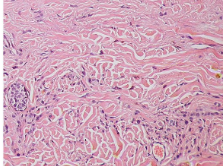

Papillary layer

Characterized by these hill-like shapes

Reticular layer